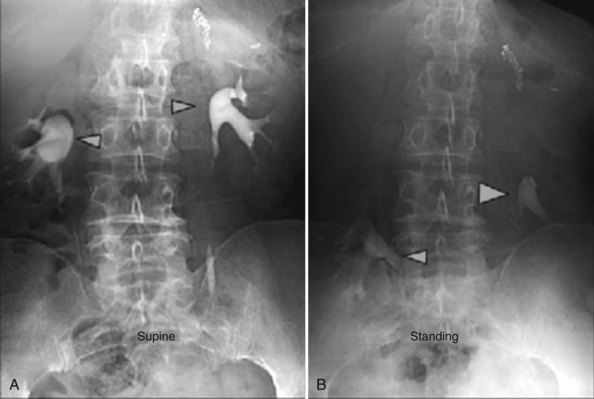

Renal ptosis, although rare, is a real cause of chronic flank or upper abdominal pain. The precise origin of symptoms is unknown, but is likely secondary to either transient ischemia or urinary obstruction (Moss, 1997). It is usually defined as the descent of the kidney by more than two vertebral bodies, but before a definitive diagnosis is made, objective proof that is associated with pain should be obtained. The typical patient with a ptotic kidney is a young, thin female who complains of pain while in an upright position. Supine and erect intravenous pyelography (IVP) can be used for diagnosis, with the finding of interest being descent of the symptomatic kidney by two vertebral bodies (Fig. 55–27). Nuclear imaging may also quantify obstruction of blood flow or drainage in the upright position. Color Doppler sonography in both the supine and upright positions can also be used to evaluate differential blood flow. If a ptotic kidney is present, the expected finding would be diminished blood flow while in the erect position. Before surgical repair, obstruction, decreased blood flow, or significant descent correlating with pain should be documented.

Figure 55–27 Intravenous pyelogram demonstrating bilateral ptotic kidneys in the supine (A) and standing (B) positions.

(From El-Moula MG, Izaki H, Kishimoto T, et al. Laparoscopic nephropexy. J Laparoendosc Adv Surg Tech A 2008;18:230–6.)